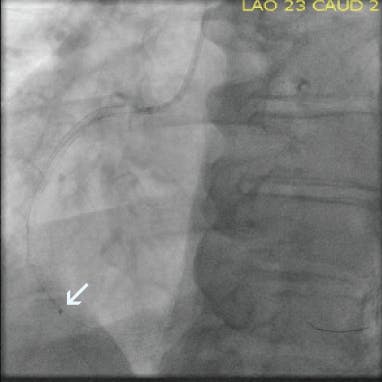

INTERVENTION

A radial approach was used for intervention. The diagnostic catheter revealed a totally occluded RCA with acute stent thrombosis and TIMI 0 flow (Figure 1). Using a whisper wire, the lesion was crossed. Two runs were then performed using CAT RX, which resulted in establishment of flow (Figure 2 and Figure 3). Subsequently, balloon dilatation was performed in the stent with a 2.5- X 20-mm compliant balloon; a 3.5- X 38-mm Resolute Onyx™ stent (Medtronic) was deployed in the mid-RCA distal to the original stent and was postdilated with a 4- X 15-mm noncompliant balloon. TIMI 3 flow was noted postprocedure, with grade 3 myocardial blush (Figure 4).

Figure 1. The occluded RCA with acute stent thrombosis.

Figure 2. Intraprocedural angiogram with CAT RX (white arrow).